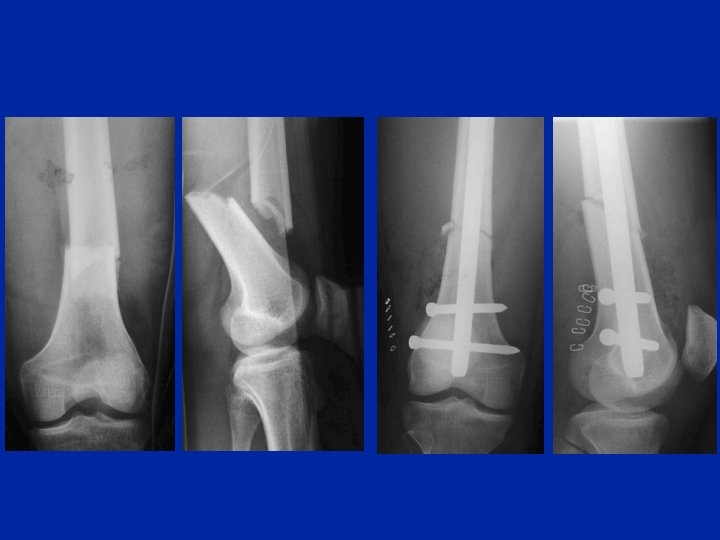

Inchiodamento retrogrado